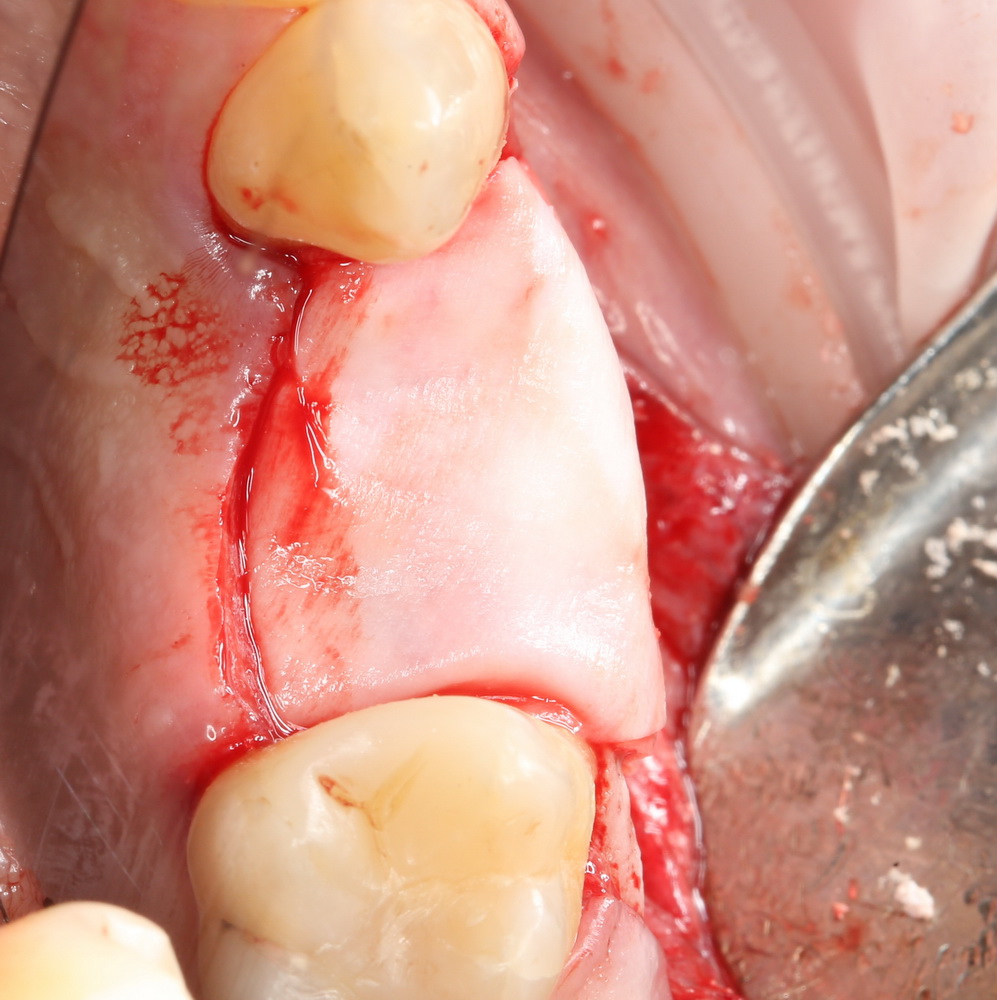

В этом случае остеопластика делается отдельной процедурой. Ее принципы точно те же, но уже без импланта. Например:

Имплантировать в таких условиях — заведомо обрекать себя на хреновый, с точки зрения эстетики и функциональности, результат. Поэтому первым этапом проводим остеопластику. Объем небольшой, использовать в таких объемах костный блок не очень рационально. Воспользуемся аутокостной стружкой и мембраной.

Сначала фиксируется BioGide. Это легко:

Затем укладывается и конфигурируется аутокостная стружка:

Если после этого BioGide намочить физраствором, им легко укрыть получившийся объем:

Для надежности можно зафиксировать пинами: